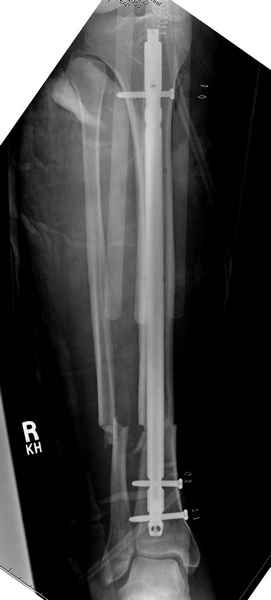

Больному с политравмой установлен наружный "spanning-bridging" фиксатор, после нескольких Irrigation&Debridment на фоне отрицательного посева из раны, через открытый участок установлен 4.5 mm Locking Plate.

На фоне фиксированного перелома бедра мероприятия по восстановлению мягкотканого покрова. Перелом голени зафиксирован после стабилизации бедра традиционным методом.